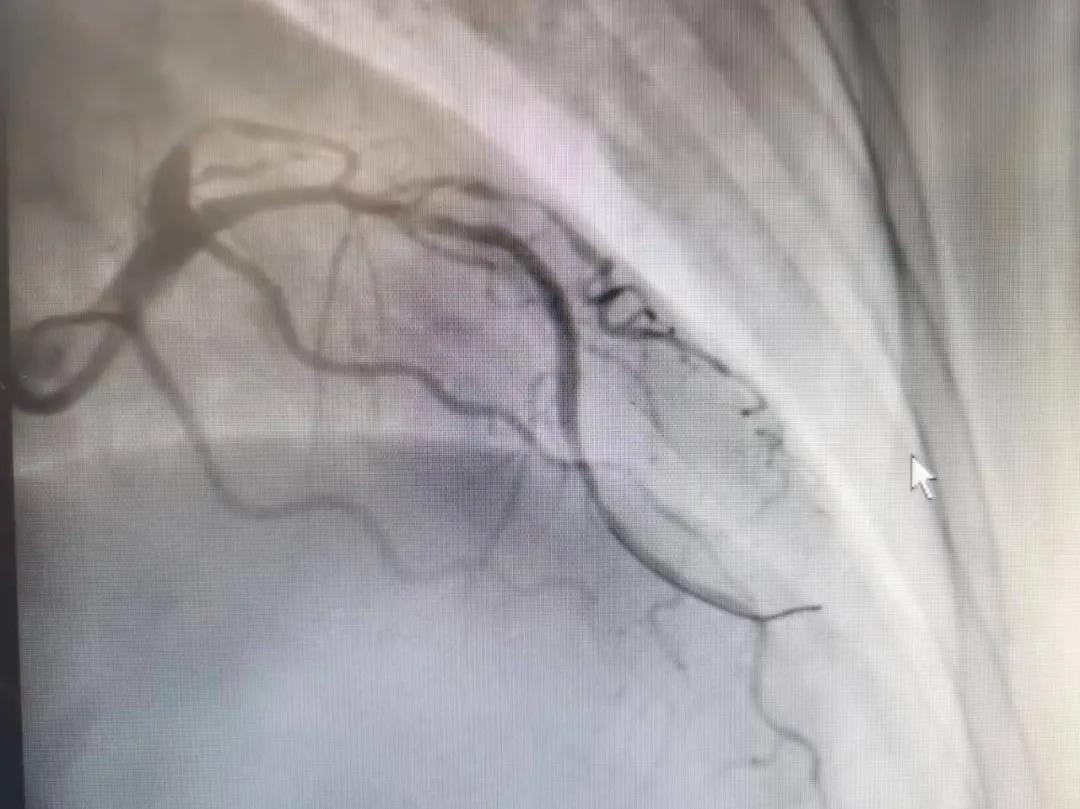

病人是位六十多歲的女性患者,有長(zhǎng)期高血壓病史,1個(gè)月前開(kāi)始出現(xiàn)胸悶胸痛,口服藥物治療效果不佳,經(jīng)朋友介紹,來(lái)到市二院心血管內(nèi)科。入院后完善冠狀動(dòng)脈造影提示:前降支全程彌漫性狹窄伴鈣化,最重95%,回旋支狹窄約85%,右冠脈全程狹窄伴鈣化,最重60%。血管內(nèi)超聲顯示右冠脈開(kāi)口面積3.36mm²,可見(jiàn)環(huán)形鈣化,考慮患者病變程度重、鈣化明顯,常規(guī)器械無(wú)法實(shí)現(xiàn)病變的良好預(yù)處理,且有很高的冠脈穿孔、血管夾層的風(fēng)險(xiǎn)。

術(shù)前

王瑾院長(zhǎng)和李慧新主任帶領(lǐng)介入團(tuán)隊(duì)充分評(píng)估,決定行前降支冠狀動(dòng)脈鈣化病變旋磨術(shù),術(shù)中應(yīng)用1.5mm旋磨頭,以15萬(wàn)-17萬(wàn)轉(zhuǎn)/分速度共對(duì)病變旋磨3次,累計(jì)旋磨時(shí)間60秒,后復(fù)查造影示鈣化明顯減輕,為后續(xù)操作創(chuàng)造了良好條件,隨后應(yīng)用預(yù)擴(kuò)張球囊、切割球囊再次處理病變,并順利植入支架1枚,復(fù)查造影顯示支架膨脹及貼壁良好,無(wú)夾層、血腫、慢血流等情況,手術(shù)順利完成。患者術(shù)后無(wú)不適,胸悶、胸痛癥狀明顯緩解,順利出院。

術(shù)后